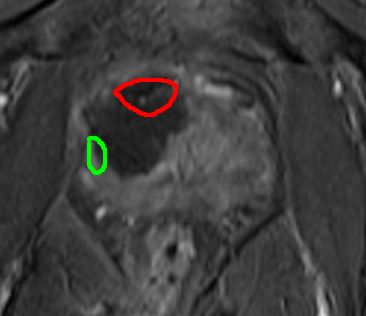

Below is my diagnostic MRI scan (September 2013), showing an "80% 1cc likely tumour" (Red areas on drawings)

My TPM Biopsy (as discussed in the video above) then confirmed it was localised prostate cancer (12mm Gleason 3+4).

Explanation: my prostate is roughly outlined in RED.

The original location of the tumour is roughly outlined in YELLOW on the 18-days image.

The ablated area is outlined in GREEN on the 18-days image.

The ablated area extended significantly below where the anterior tumour had been (see annotated sketch - original tumour outlined in red).

But an advantage may be that it may have also partially destroyed the peripheral 3 + 3 cancer on the right hand side, (marked as a green area). Even though I had asked him not to, the cryo could not be controlled precisely enough not to destroy that.